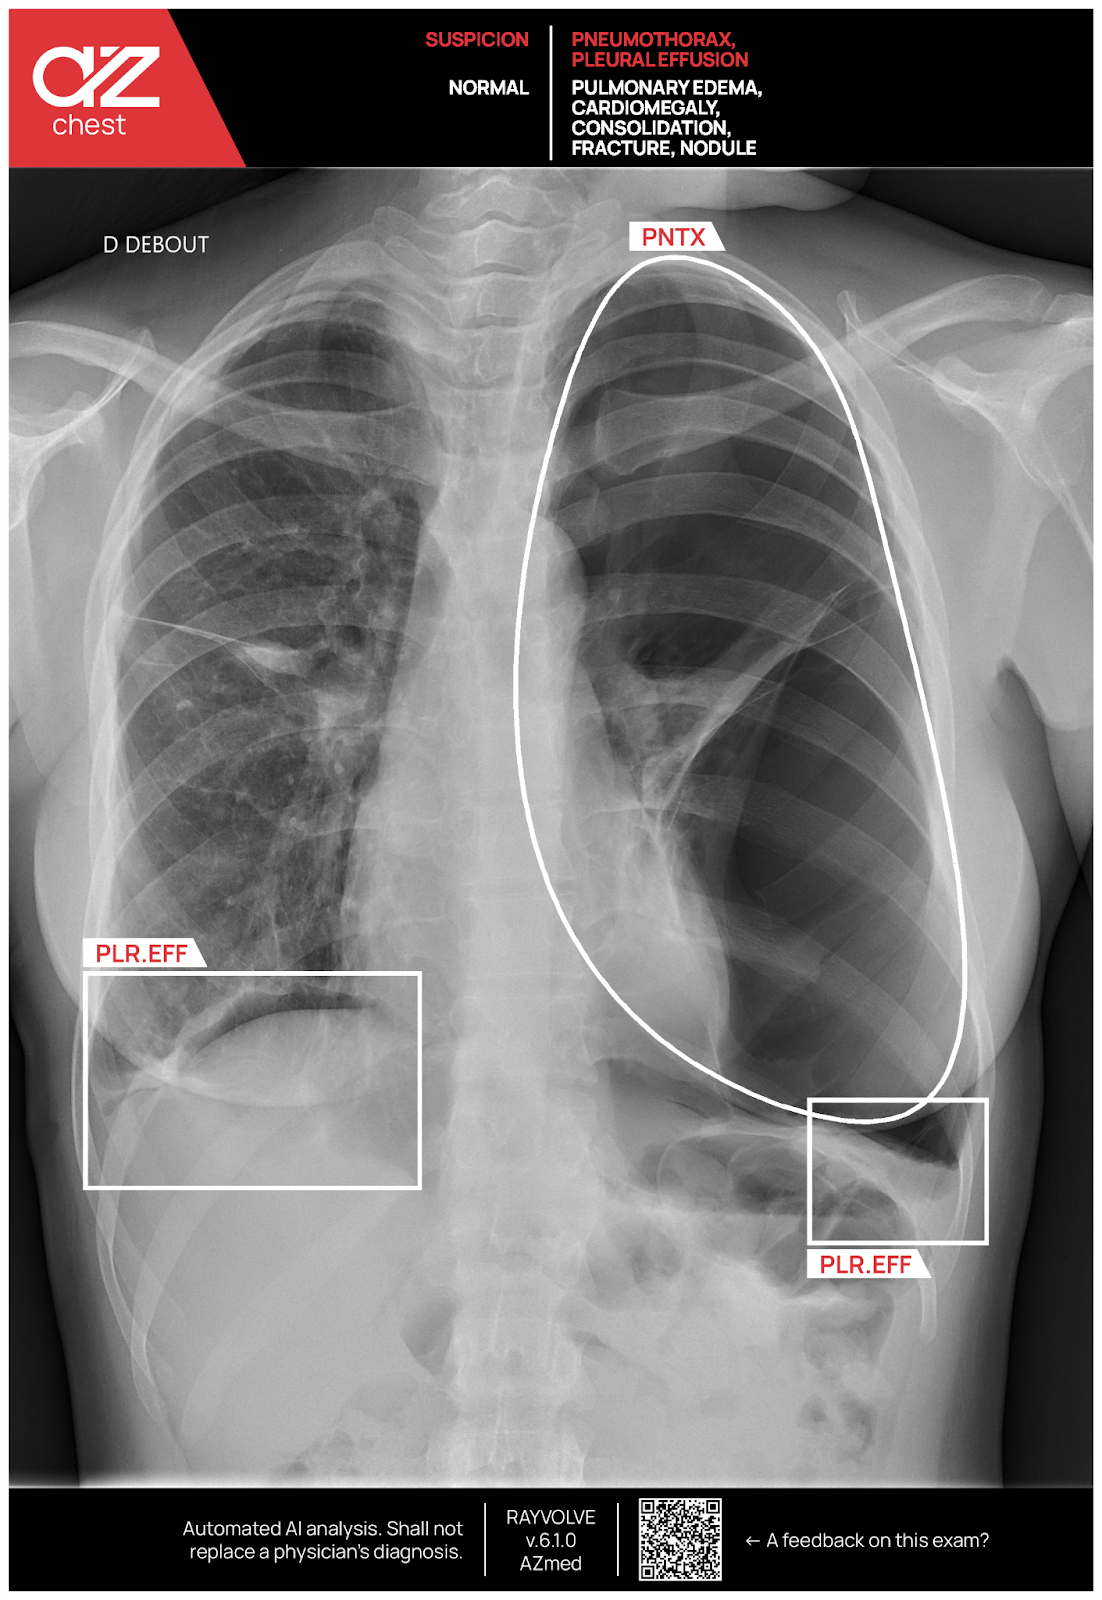

O AZchest analisa cada radiografia frontal e lateral do tórax para detectar sete doenças pulmonares e cardíacas comuns: nódulos pulmonares, fraturas de costelas, cardiomegalia (coração aumentado), consolidação (espaço aéreo preenchido), derrame pleural (líquido ao redor dos pulmões), pneumotórax (vazamento de ar devido a ruptura pulmonar) e edema pulmonar (líquido no tecido pulmonar).

Novo recurso: contorno de PTX para pneumotórax

As caixas delimitadoras são rápidas, mas cortam os cantos, literalmente. Para pneumotórax (PTX), o AZchest pode mudar para um contorno suave que acompanha a borda real do ar escapado. Assim, os radiologistas veem a forma e a profundidade reais, e não um quadrado aproximado.

Por que isso é importante? Primeiro, o contorno curvo fica bem na borda pleural, de modo que as verificações de tamanho permanecem estáveis do dia à noite. Segundo, a linha precisa orienta a colocação do dreno torácico e mostra o encolhimento nas imagens de acompanhamento, aumentando a confiança clínica.

Enquanto isso, todas as outras descobertas continuam em suas caixas organizadas, para que a tela permaneça arrumada. Um clique ativa ou desativa o contorno PTX, oferecendo mais detalhes aos usuários avançados, enquanto os usuários iniciantes desfrutam de uma visualização familiar.